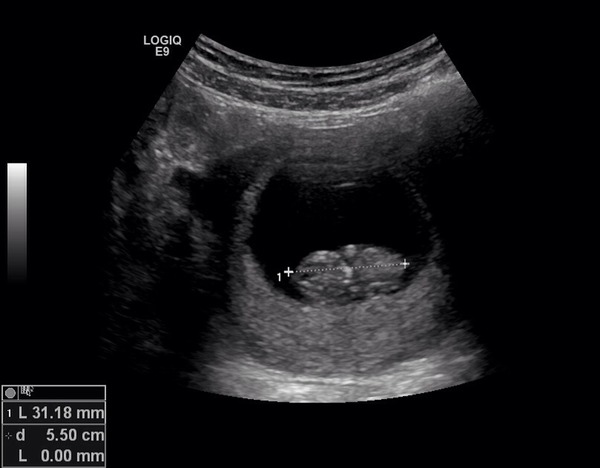

Leela5 · 18/12/2014 17:33

Here's my scan from yesterday, 9+5

Love you can see the limbs, it was wriggling too!

July thread - we are nearing the end of the first trimester, announcements will be made soon!